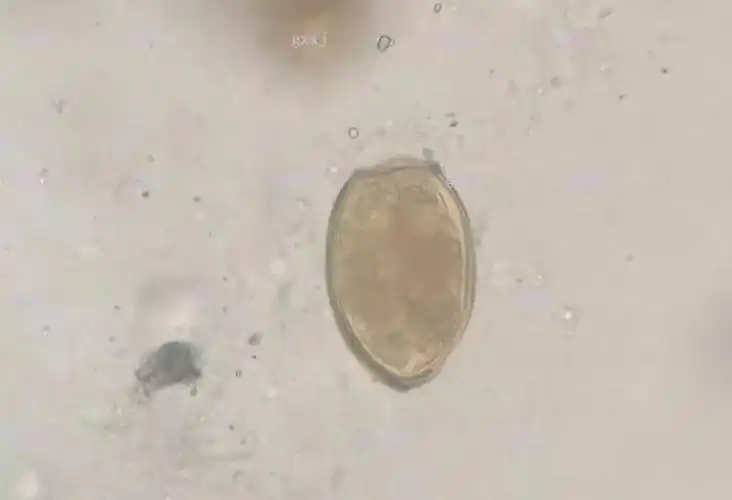

寄生虫形态·常见寄生虫卵